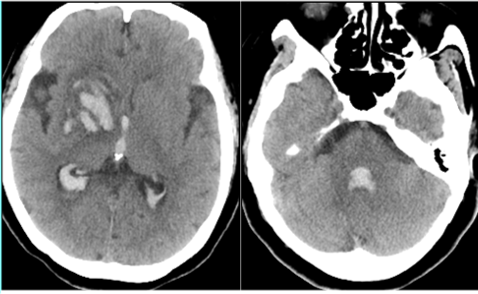

病例2

男,49歲,因“突發頭痛7小時”急診入院

患者自訴7小時前無明顯誘因下出現額頂部頭痛,呈持續性脹痛,至當地醫院查頭顱CT提示腦室出血,患者為求進一步診治,轉至我院急診

CT+MRI